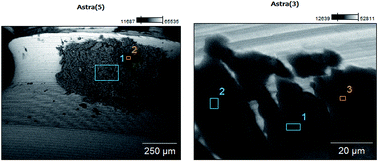

The main goal of the study was to determine the compounds released from titanium into the overlying oral mucosa and the other metals found in two-stage dental intra-osseous implants. The determined concentration of the metals was as follows: titanium from 1.7 to 13.1 μg g−1, nickel 10.0–0.8 μg g−1, aluminum 5.3–100.5 μg g−1, zinc 16.1–118.8 μg g−1, and copper 0.3–13.6 μg g−1, respectively. Additionally, we also present the results of experiments carried out to determine the release of metal ions from two implant systems (Astra and Dentium) into a solution of lactic acid (1%). The quantitative analysis of the metal ions was performed by means of an emission spectroscope by inductively coupled plasma ICP-OES. Studies were also carried out on the surfaces of different implant systems, including: Osteoplant, Astra, Dentium, SKY, Neoss as well as Biomet. The research involved the use of scanning electron microscopy to determine the chemical composition and quality of these systems.